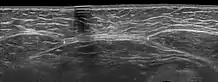

Ультразвукове дослідження може знадобитися в окремих випадках, наприклад за наявності надмірної ваги у пацієнтки, коли огляд і пальпація не дають однозначної чіткої картини. УЗД добре бачить шари передньої черевної стінки і дозволяє точно виміряти ширину діастаза на різних рівнях.